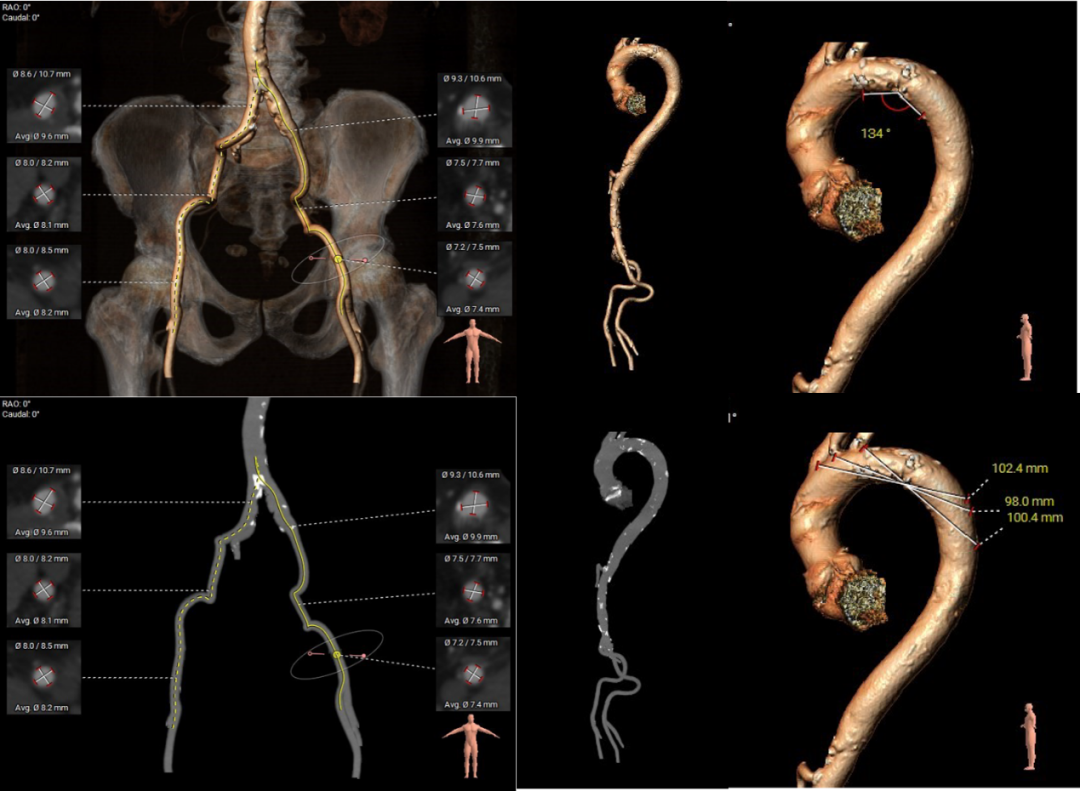

主动脉根部评估:

三叶式主动脉瓣,瓣环周长78.4mm,平均周长径24.9mm,左冠脉开口高度大于瓣叶长度,综合考虑冠脉风险低,LVOT周长径24.9mm,升主动脉直径30.8mm。

左冠高度17.5mm右冠高度22.6mm,右冠脉开口高度大于瓣叶长度,SOV瓦式窦:平均周长径38.2mm,术中仍球囊预扩须密切注意冠脉灌注,STJ周长径29.4mm。

瓣叶重度钙化伴增厚,钙化分布不均匀,HU596积分930mm²。

左室腔内径偏小,心室壁增厚明显。

主动脉弓角度与宽度可,心脏水平夹角53°,非横位心,外周血管内散见钙化灶,双侧入路血管内径良好,整体入路血管条件较好。

①患者为Type 1二叶式主动脉瓣,左、右冠瓣叶融合钙化脊,瓣叶重度钙化伴增厚,且钙化分布不均,瓣环与水平夹角较大,瓣周漏及瓣膜位移风险高。术中选择23mm球囊预扩,减小瓣膜位移风险,并在预扩时密切注意根部限制性结构打开情况,及双侧冠脉灌注情况。

②患者心室腔较小,导丝塑性小弯型,术中严格管理超硬导丝,防止超硬导丝弹出心室或者钩住瓣膜。

③综合评估患者瓣环、流出道、瓦氏窦、STJ等结构,选择直径26mm瓣膜。

④患者整体血管情况良好,右侧股动脉稍扭曲,术中大鞘及输送器轻柔操作,避免外周血管损伤,必要时备snare辅助。

⑤患者瓣上结构限制严重,术中须严格控制瓣膜释放深度,选择瓣上3mm左右释放。